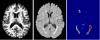

FLEXCONN (Fast Lesion Extraction using Convolutional Neural Networks) is a toolbox for segmenting white matter lesions from multi-contrast MR images. Using T1-w and FLAIR images, a fully convolutional neural network (CNN) is trained using manually labeled training data. The trained CNN model can be applied to pre-processed pair of T1 and FLAIR images to generate a lesion membership as well as a hard segmentation. The algorithm is described in the following paper: